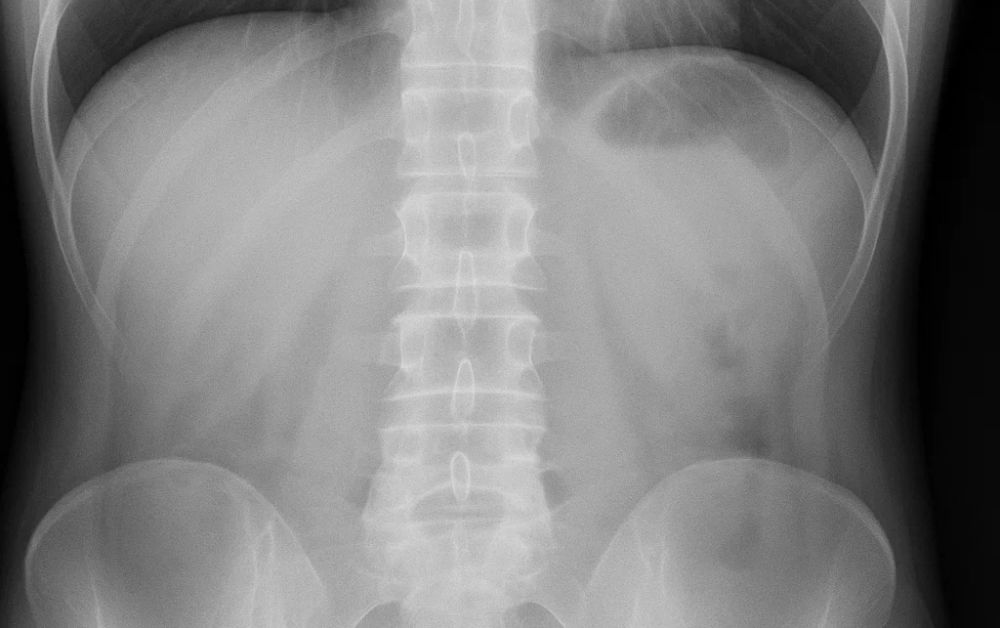

Portable X-ray systems are compact, mobile imaging systems designed to produce high-quality radiographs of patients who are unable to visit conventional X-ray rooms. These include portable X-ray generators, digital detectors, and connected software ,all in a highly mobile format that can be quickly moved on-site to any field within the hospital system – or beyond.

2. Wireless Digital Radiography Systems

• Orthopedic injury assessment